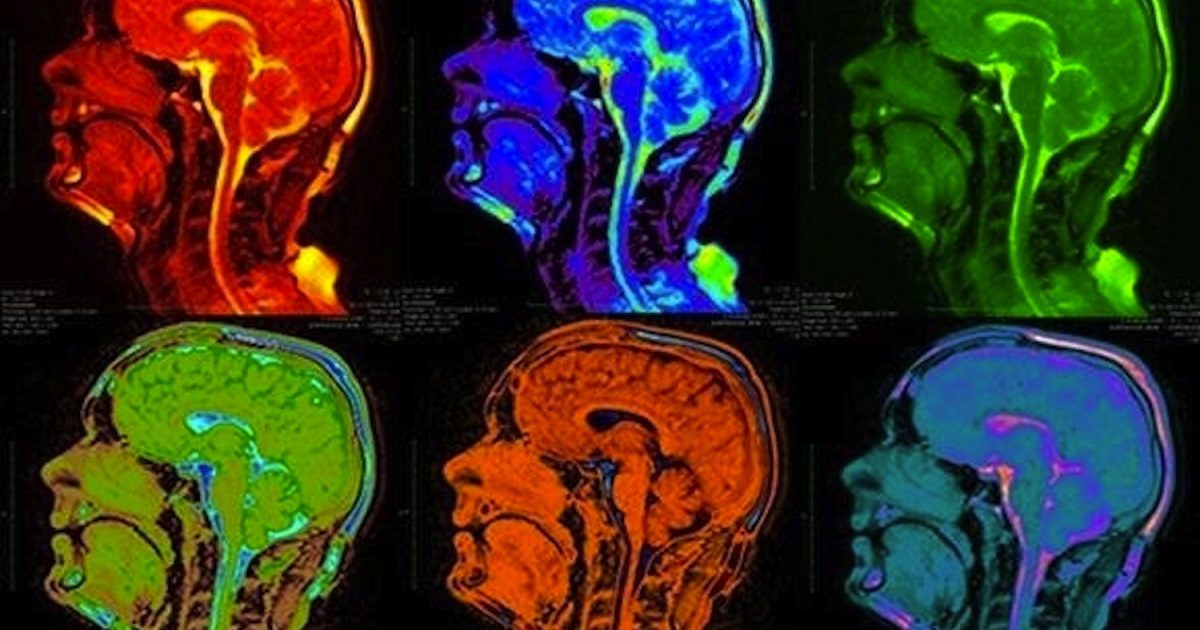

Naime, za potrebe studije 6 ispitanika bilo je dužno preslušati 40 pjesama raznoraznih žanrova, a znanstvenici su koristeći magnetsku rezonancu i tehniku “dekodiranja mozga” nastojali utvrditi koju pjesmu slušaju u određenom trenutku, stavljajući u korelaciju moždane reakcije i karakteristike muzike koju čuju kao što su tonalitet, dinamika, boja i ritam. Čitajući moždani uzorak sudionika, kompjuter je s preciznošću od 85% prepoznao “živčani otisak prsta” svake pjesme.